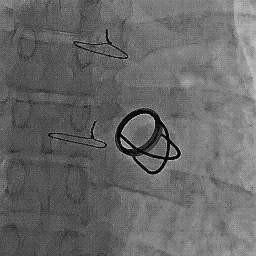

Since the lower end of esophagus just hugs the left atrium , this anatomical concept was successfully exploited for imaging heart in TEE.Now cardiac anesthetists routinely use the esophagus as an imaging port during complex mitral valve surgeries.

Note , the esophagus does a friendly hug as it crosses the heart posteriorly .It is a perfect anatomical sense , to Image and pace the heart from within the esophagus !

It was in 1980 , a dramatic concept was conceived . Why not use the esophagus as an access for pacing the heart

after all , it reaches as close as possible to the heart !